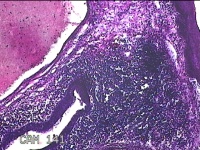

3、7、11点肿物

性别

男

年龄

34岁

临床诊断

1.混合痔 2.肛裂

一般病史

大便出血半年,伴粘液便。

标本名称

大体所见

灰白暗红色肿物1.8x1x0.3cm两个,表面糜烂。

痔是有的。